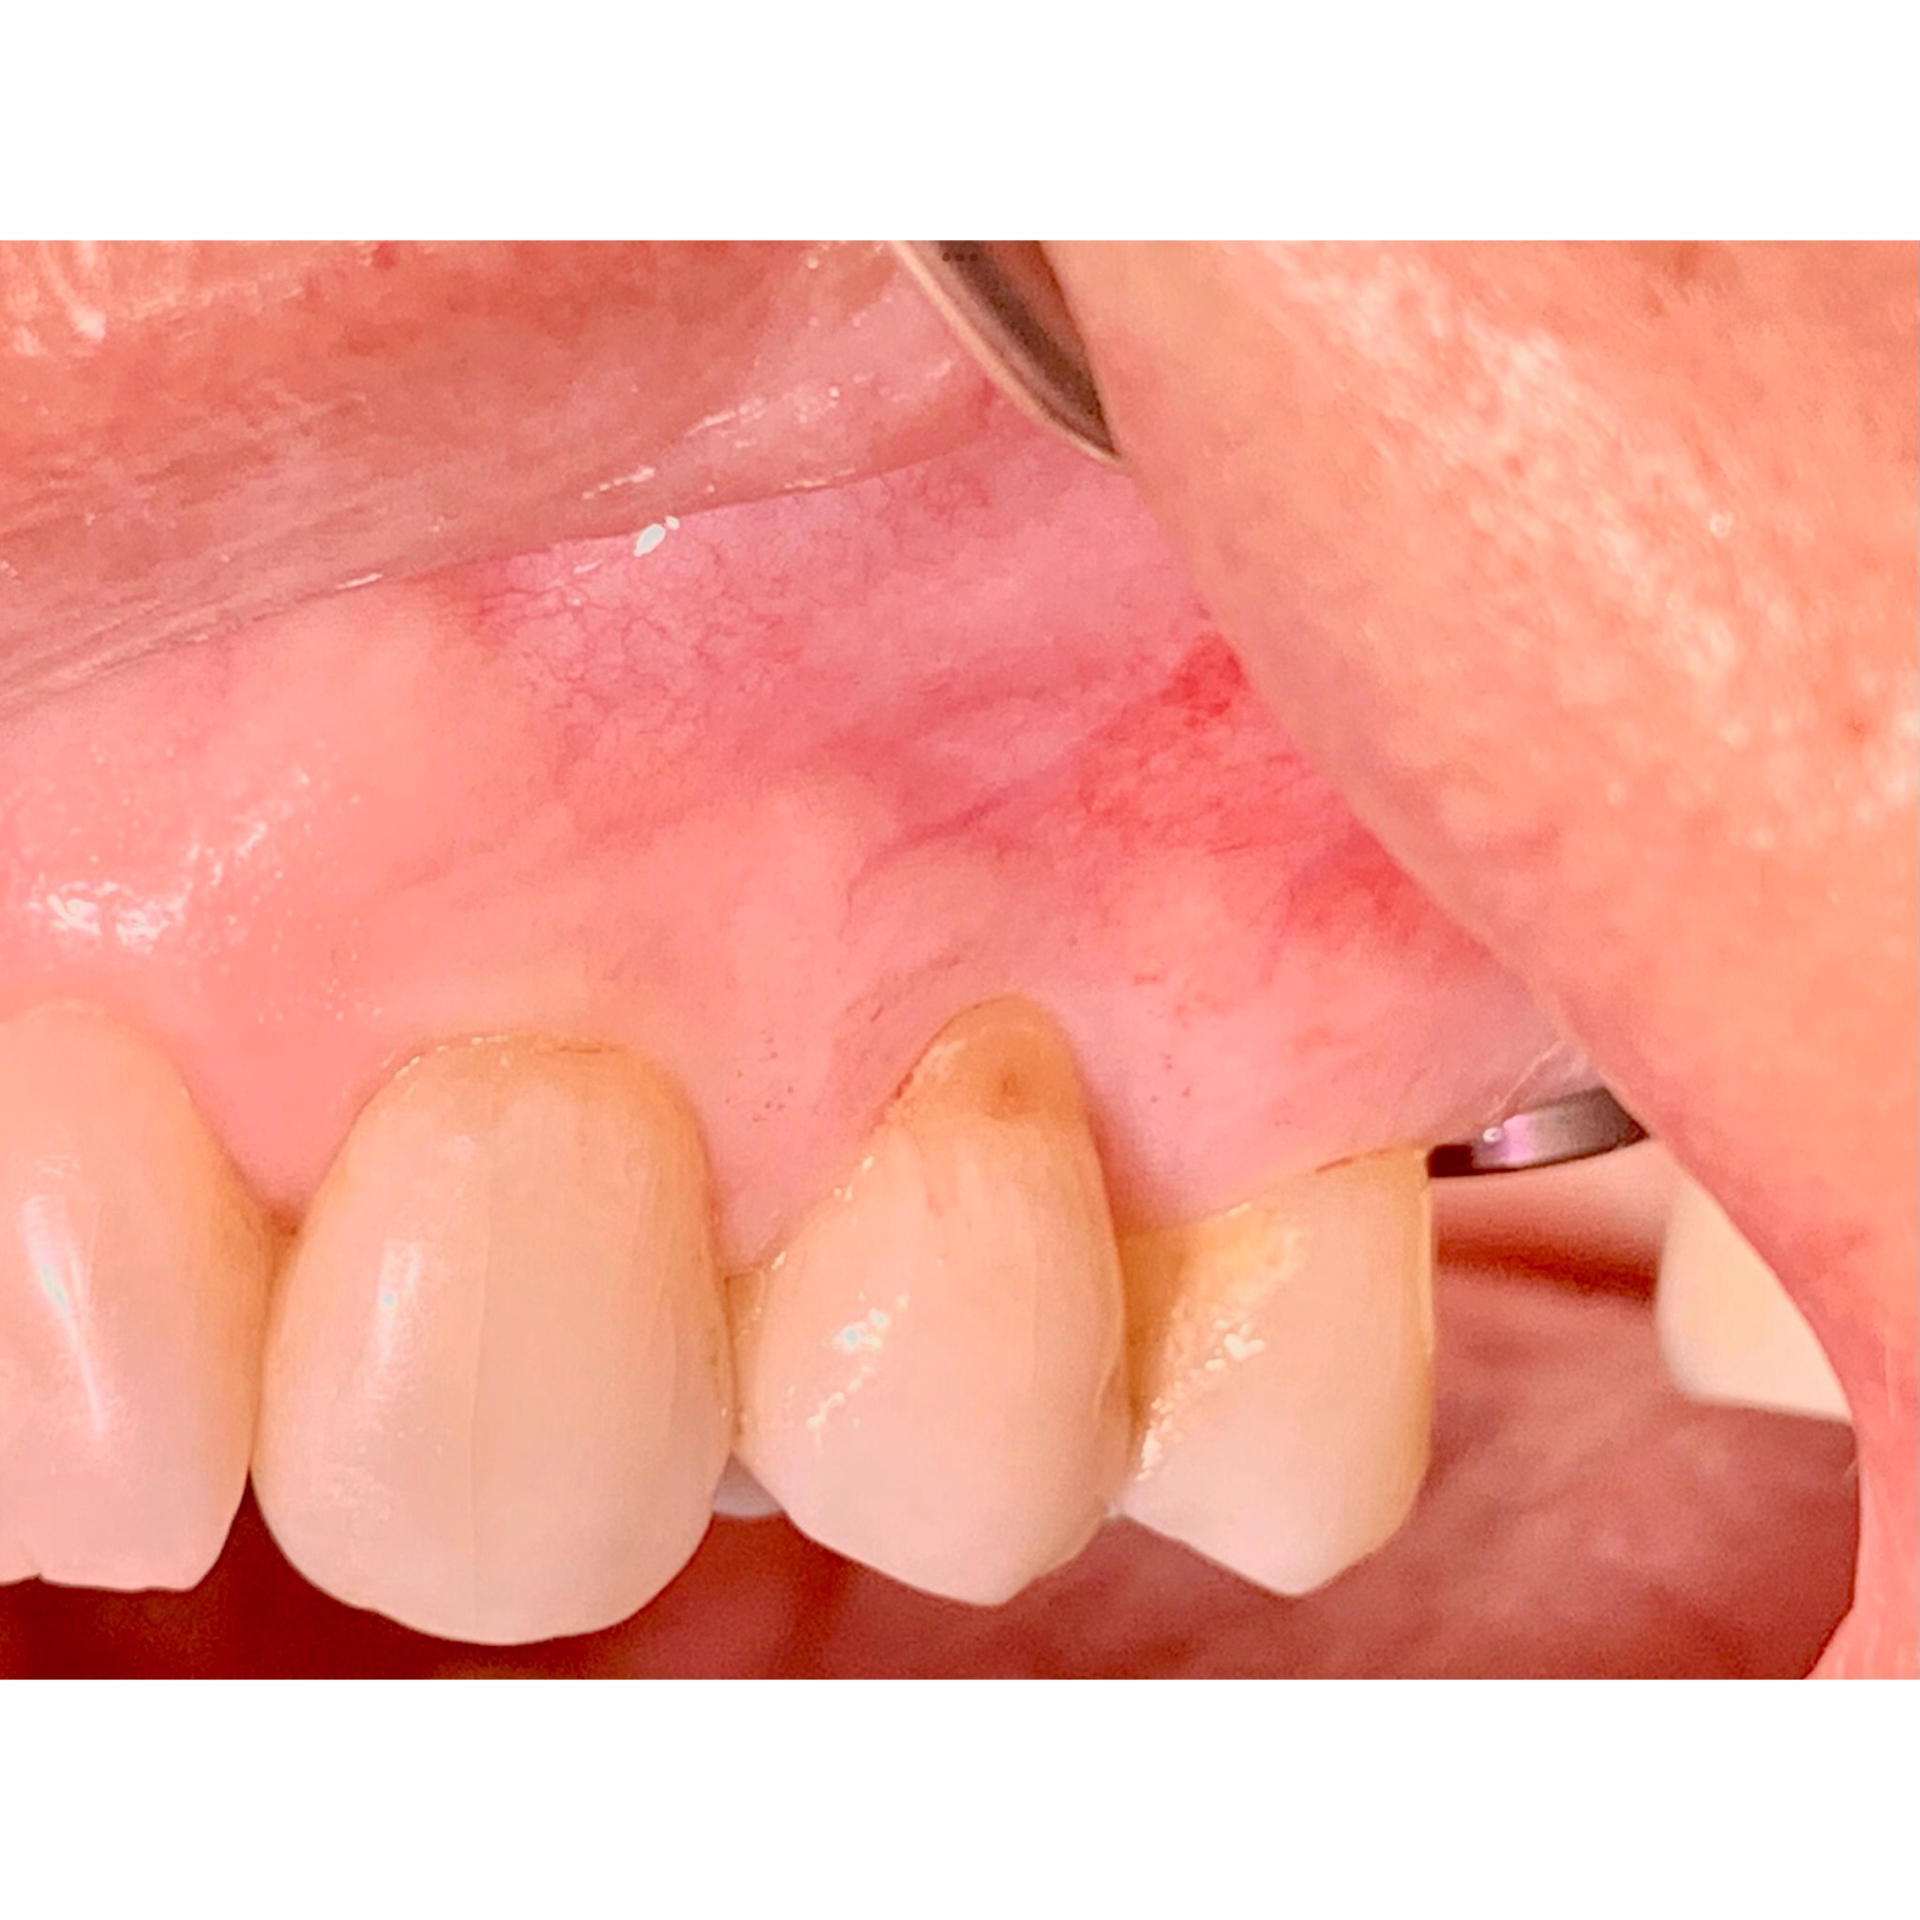

Avant et après greffe de gencive